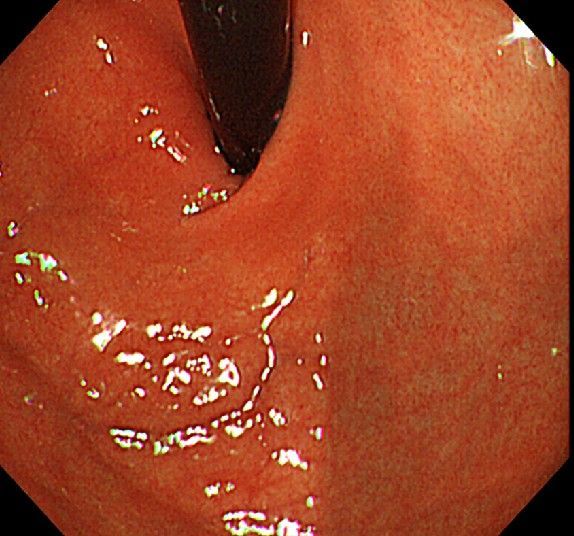

위 내시경을 찍었는데 위염 종류 사진을 알 수 있을까요? (사진 많습니다..)

한달 전 쯤에 소화불량과 속쓰림이 3개월 동안 약을 먹어도 낫지 않아 위 내시경을 찍었는데 위에 염증이 많이 있다는 이야기를 들었습니다...그런데 상태가 얼마나 안 좋은지 어떤 종류의 위염인지에 대해서는 물어봐도 안 알려주셔서 여기에라도 올려서 여쭈어봅니다... 제 상태가 얼마나 심각한 걸까요..

사진상으로 보아서는 정상에 가까운 점막상태이거나 약간의 표재성 위염이 있는 정도로 보입니다.

홍반성 위염이 있으며 경증의 역류성 식도염이 있습니다